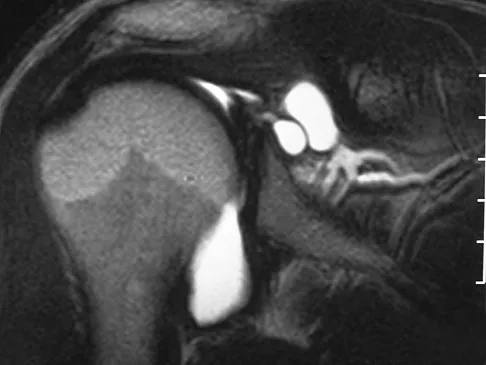

A patient reports persistent anterior shoulder pain following a forceful external rotation injury to the shoulder. An MRI scan is shown in Figure 4. The patient remains symptomatic despite 3 months of nonsurgical management. Treatment should now consist of

Explanation

The MRI scan reveals a subscapularis tear with a biceps that is out of the groove. Treatment in this patient is most predictable if the subscapularis is repaired. The biceps should either be tenodesed or tenotomized since it is unstable. Recentering of the biceps has been found to be unpredictable. Treatment of these lesions has been shown to have better results if the biceps is either released or tenodesed. This prevents recurrent biceps symptoms that can be source of surgical failure. Edwards TB, Walch G, Sirvenaux F, et al: Repair of tears of the subscapularis: Surgical technique. J Bone Joint Surg Am 2006;88:1-10. Deutsch A, Altcheck DW, Veltri DM, et al: Traumatic tears of the subscapularis tendon: Clinical diagnosis, magnetic resonance imaging findings, and operative treatment. Am J Sports Med 1997;25:13-22.